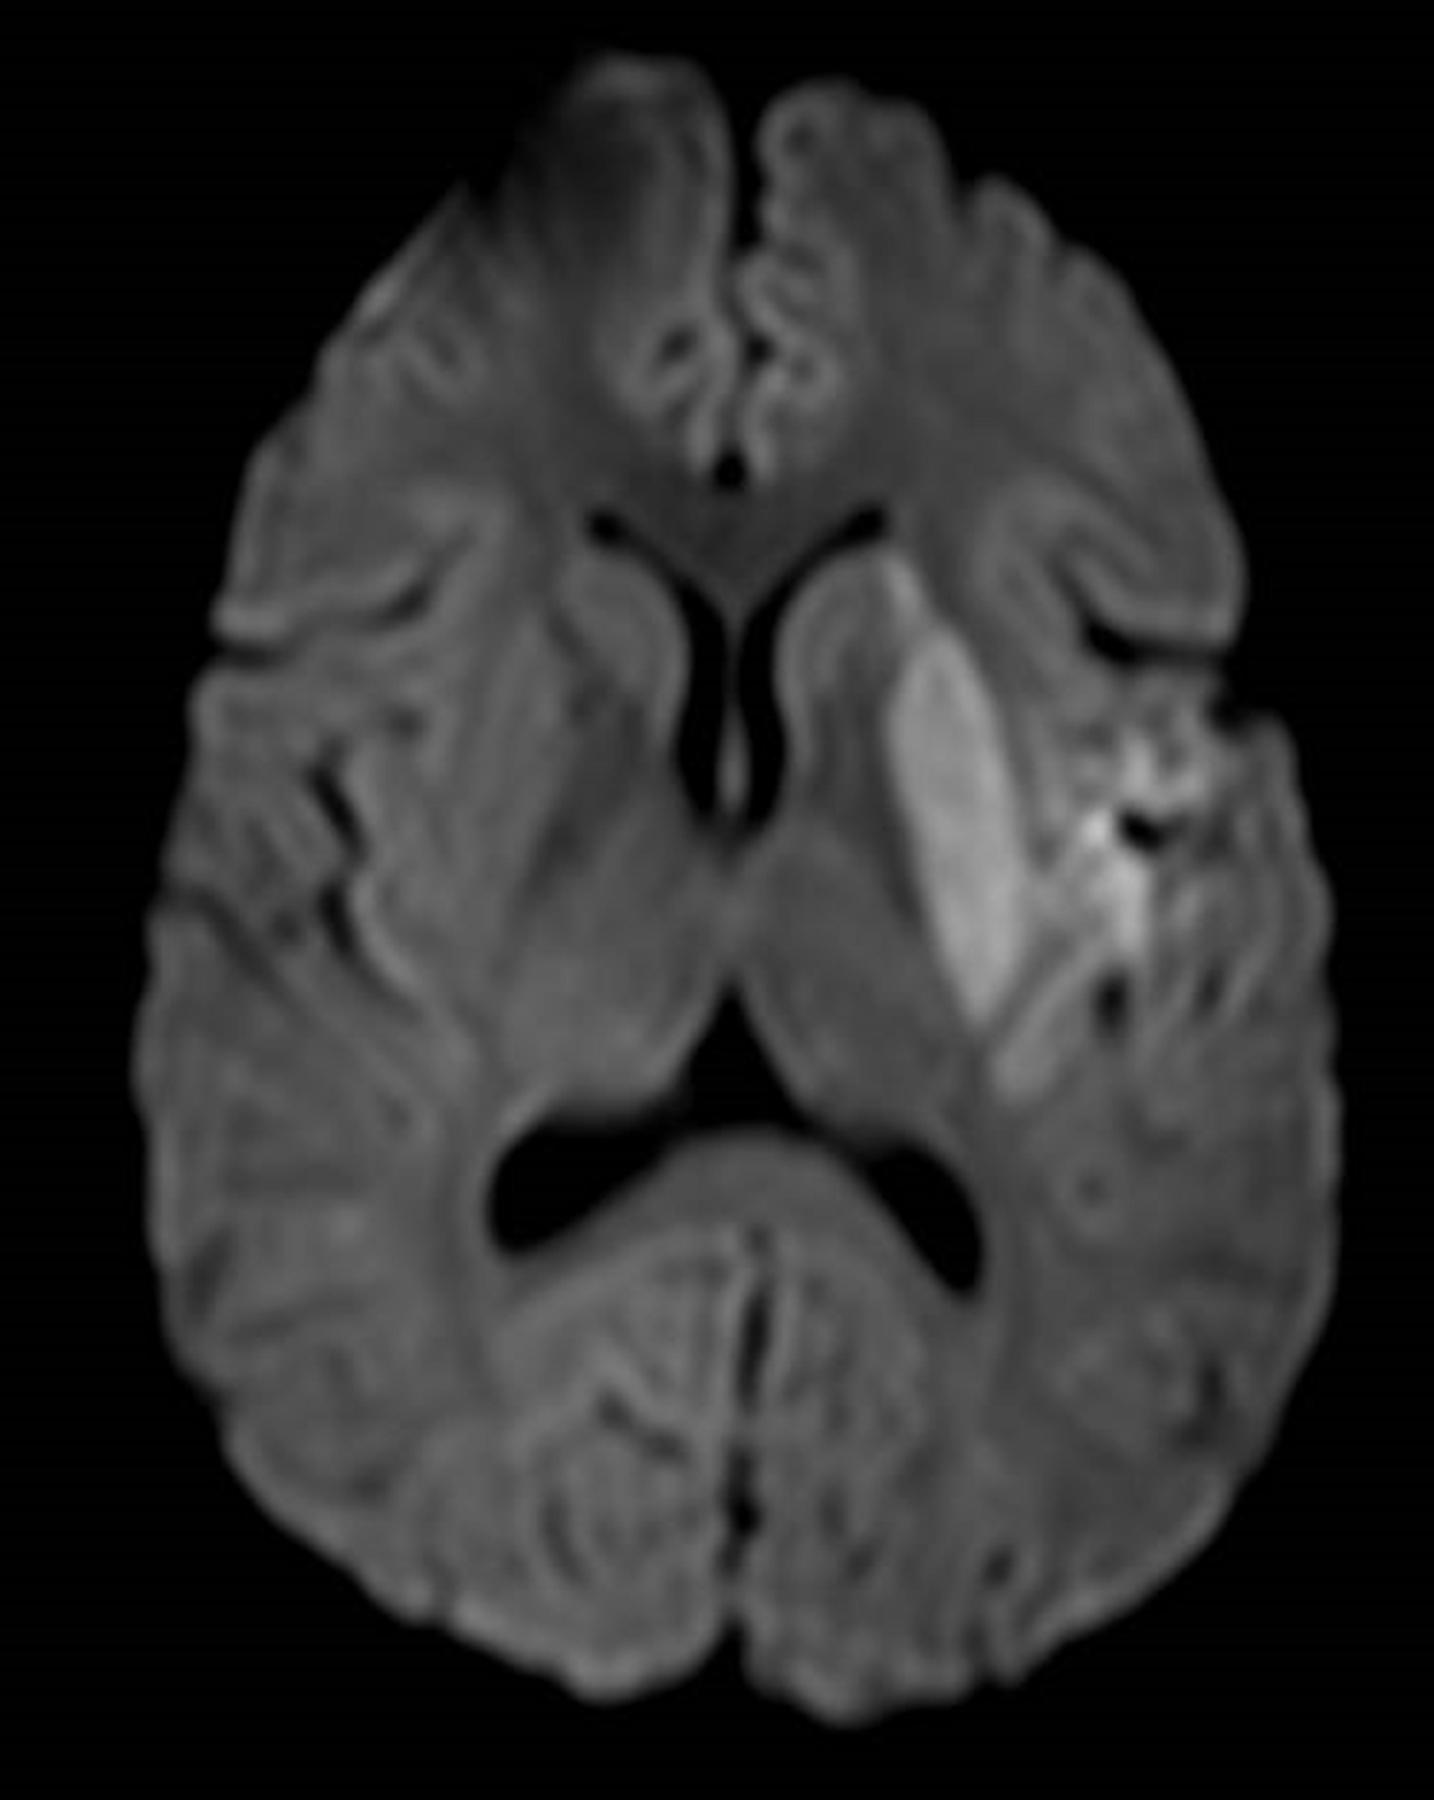

He was great: Dr. Leung has been amazing. He spent so much more time with me than any other doctor, but also much more time than I would have assumed he could spend with me. No one else had ever shown me the scans from the MRI or CT scans. He took me through each one of the scans and showed me where the previous stroke was. He explained every single thing from treatment options to making sure I understood why the stroke could have possibly could have happened.